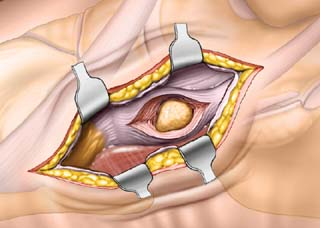

비 수술적 치료에도 호전이 안될 경우, 부주상골 제거술 또는 고정술이 필요할 수 있습니다.

발의 정상적기능에는 부주상골이 필요치 않으므로 제거 후 재활치료를 통해 증상을 호전 시킬 수 있습니다. 때때로 경우에 따라 부주상골 제거 후 후경골근 힘줄 고정술도 필요할 수 있으며 수술은 통증 및 증상완화에 90%이상의 효과를 보입니다.